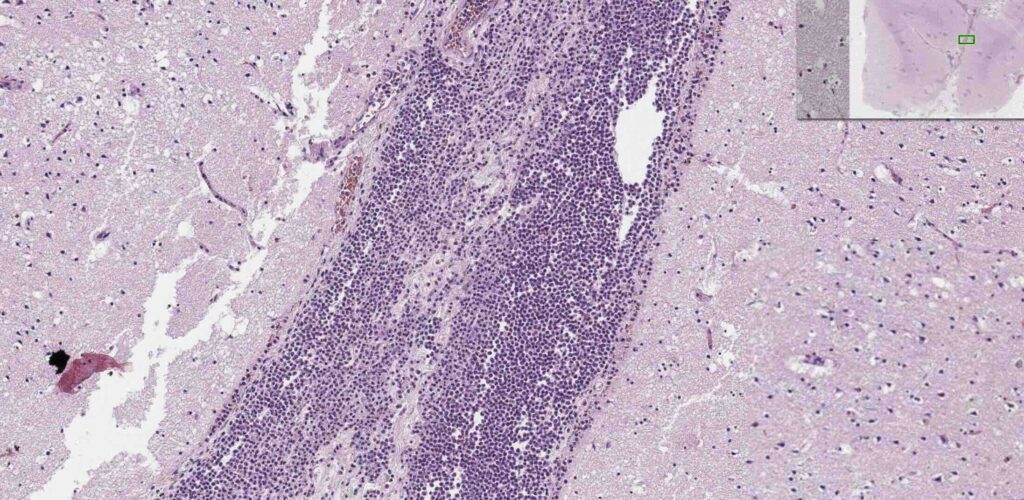

Jeg er ikke patolog, men jeg tror, at man her ser et HE-farvet snit af cortex hos 81-årig kvinde med meningitis. Man kigger ned i sulcus, og ser at den er fuldstændigt udtamponeret af polymorfnukleære celler. Bragt med tilladelse fra University of Leeds og https://www.virtualpathology.leeds.ac.uk/

Kigger man på obducerede hjerner efter bakteriel meningitis, så finder man ødem, hydrocephalus, petekielle blødninger, nekrotiske læsioner i cortex og subcortikalt, tabte myelinfibre i den hvide substans og hippocampas apoptose. Post-mortem-studier efter pneumokokmeningitis har primært fundet bakterier i subarachnoidea og i vaskulaturet, hvilket taler for, at hjerneskaden ved meningitis primært er medieret af vaskulitis, vasospasmer, cerebral hypoperfusion, iskæmi og infarkt (van de Beek, 2016).